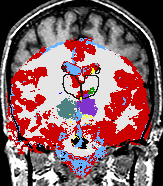

| We use a Bayesian modeling approach for image segmentation, in which we build a parametric computational model of how an MRI image around the hippocampal area is generated. The model incorporates a prior distribution that makes predictions about where neuroanatomical labels typically occur throughout the image, and is based on a generalization of probabilistic atlases that uses a deformable, compact tetrahedral mesh representation. The model also includes a likelihood distribution that predicts how a label image, where each voxel is assigned a unique neuroanatomical label, translates into an MRI image, where each voxel has an intensity.

Given an image to be segmented, we first estimate the parameters of the model that are most probable in light of the data. The parameter estimation involves finding the deformation that optimally warps the mesh-based probabilistic atlas onto the image under study, as well as finding the mean intensity and the intensity variance for each of the hippocampal subfields. Once these parameters are estimated, the most probable image segmentation is obtained. | |